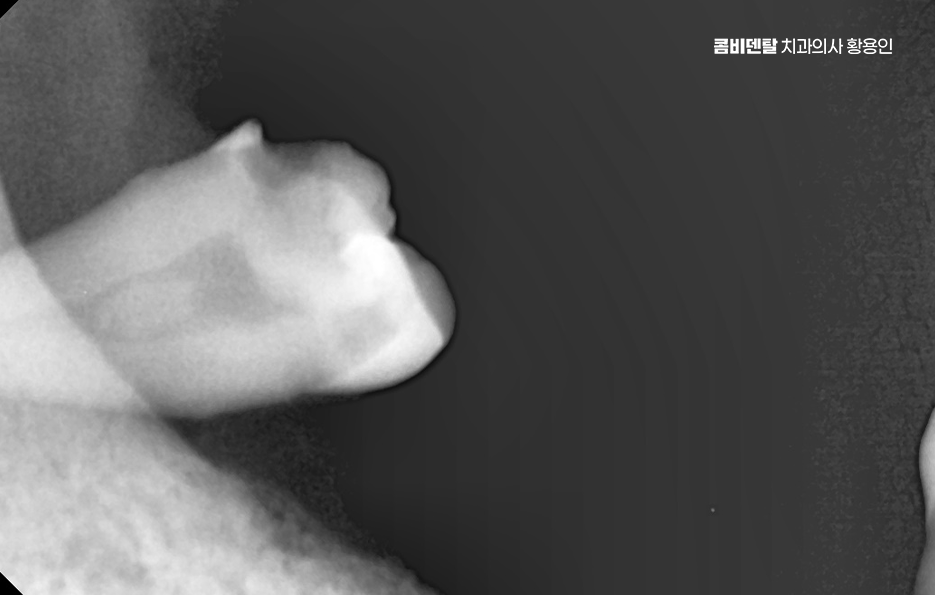

어금니 발치후 임플란트 안하면 먼저 생기는 문제는 치아 이동 현상으로 사람의 치아는 서로 의지하면서 균형을 맞추고 있는데, 어금니 하나가 빠지게 되면 그 자리를 메꾸기 위해 옆 치아들이 점점 쓰러지듯이 기울어지며 또 위아래 맞물리던 치아는 상대 치아가 사라지면 아래로 내려오거나 위로 솟구치면서 위치가 틀어질 수 있어요

그렇다면 어금니 발치 후, 임플란트를 잘 받기 위한 방법은 뭐냐 하면 첫 번째는 시기를 놓치지 않는 것인데 발치 후 3개월 내에는 임플란트를 심는 게 이상적이며 사실 요즘은 경우에 따라 ‘즉시 식립’이라고 해서 발치 당일에 임플란트를 심는 경우도 많아지고 있기 때문에 발치와 함께 임플란트 치료 계획을 세우는 것이 이상적이라 할 수 있어요